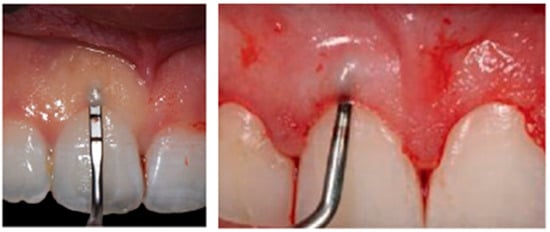

2.4. Surgical Approach and Clinical Recommendations